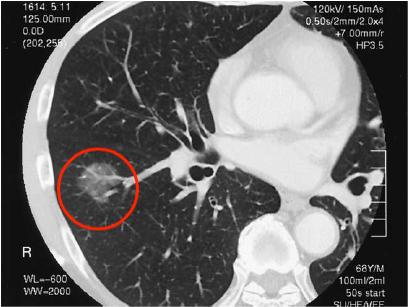

磨玻璃结节是指在胸部薄层CT扫描时发现密度增高的、云雾状的箔片影或者类圆形的结节,因为看上去像磨玻璃样,所以称为磨玻璃结节。

下图就是一个典型磨玻璃结节